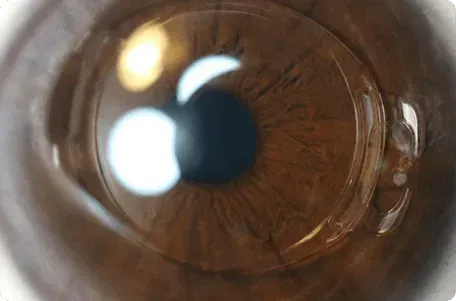

The femto-second laser, used for cutting the flap during an operation using the femto-lasik technique, offers near perfect cutting quality and precision.

Femto Lasik

Most efficient, precise laser eye treatment technology